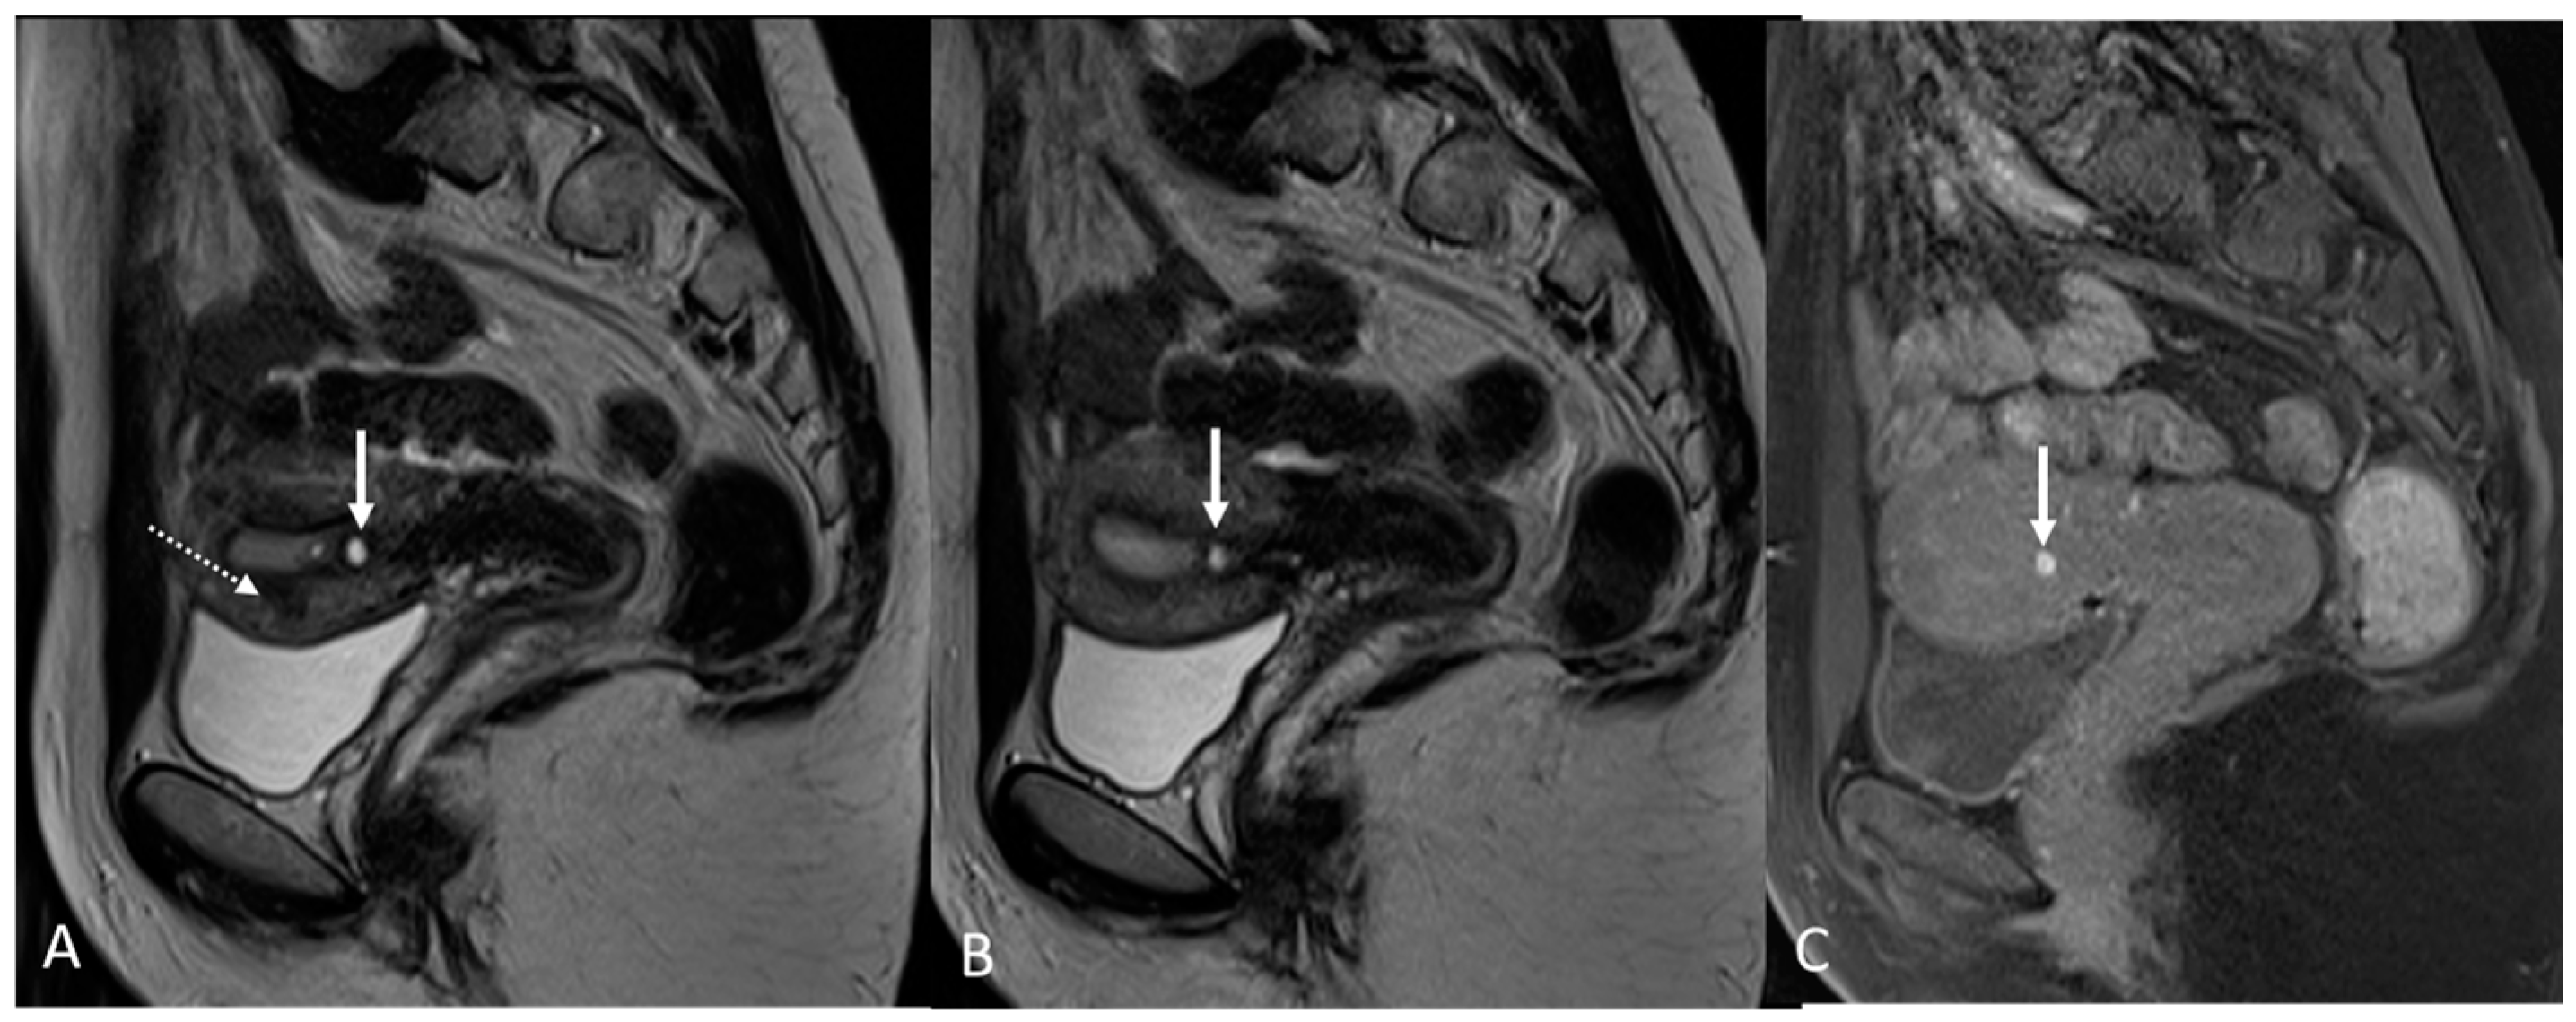

In order to perform a correct evaluation, the bladder must be at a degree of repletion suitable for the correct study of its walls and its lumen: those nodules or masses are responsible for the loss of the normal hypointense signal of the muscularis layer on T2WI. Hemorrhagic content may also be seen as hyperintense foci on T1WI, and it is also possible to observe hyperintense cystic areas on T2WI [7,14] (Figure 1).

Figure 1.

Localization of endometriosis in the vesico-uterine pouch in a 42-year-old female. (A) Sagittal T2WI (black arrow); (B) Sagittal fat-suppressed T1WI (white arrow); (C) Coronal T2WI (black arrow).

In the case of a mural mass protruding into the lumen, mucosal or submucosal edema is well depicted on T2WI [40].